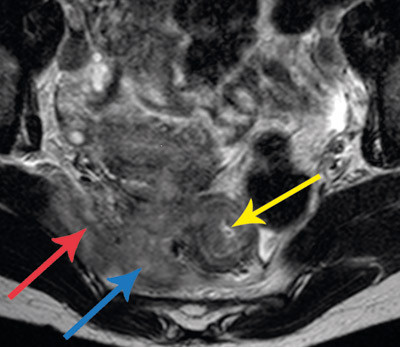

At A israelii gir en granulomatøs, suppurativ betennelse med fibrosedanning, gjenspeiles i bildediagnostiske undersøkelser. Et typisk funn er tykkveggede, cystiske tumorer med dårlig avgrensning til omkringliggende vev. De kan til forveksling likne maligne prosesser (fig 1, fig 2).

Ved computertomografisk (CT) undersøkelse dominerer som oftest solid vev, som har inhomogen kontrastoppladning i 80 % av tilfellene, med innslag av lavere tetthet eller tykkveggede cyster. Ved magnetisk resonanstomografi (MR) ses tilsvarende solid vev med innslag av flytende innhold. Signalet i de solide komponentene varierer med grad av fibrose, ved uttalt fibrose er det lavere T2-signal enn forventet ved maligne prosesser (som vanligvis inneholder mer væske) (26).

A israelii produserer proteolytiske enzymer som gir tendens til betydelig lokal infiltrasjon, som ved CT- og MR-undersøkelser ses som utvisking av normale barrierer og infiltrasjon i omliggende vev (27). Bakteriens størrelse forhindrer lymfespredning, og forstørrede lymfeknuter ses derfor sjelden (27).